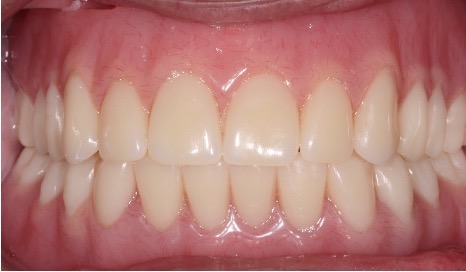

Dentures can be hard to tolerate. Dental implants can be used to help keep dentures in place but still allow removal for cleaning. It is an excellent and cost effective way to replace multiple teeth. This can also be used in combination with partial dentures.